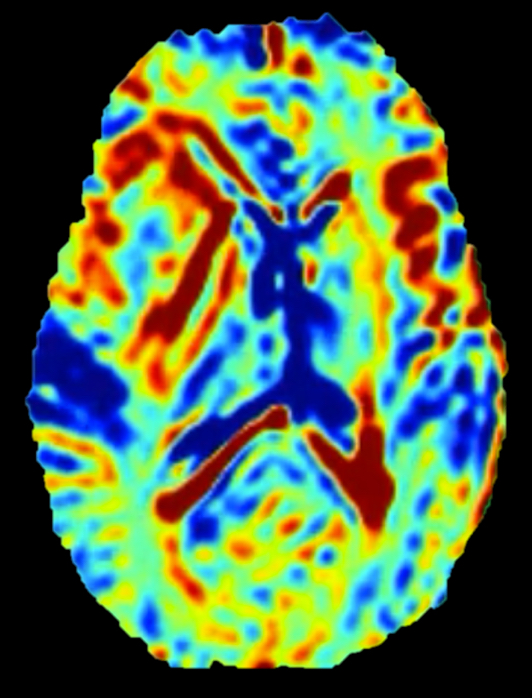

Ik noemde verder al dat doorbloeding een belangrijk fysiologisch proces is, dat ons kan helpen meer over een ziekteproces te leren en de ziekte te diagnosticeren. We weten bijvoorbeeld dat hersentumoren over het algemeen snel gaan groeien zijn als ze sterk doorbloed zijn.

Dit is de doorbloeding in de tumor van onze patiënte, waarbij de koele kleuren aangeven dat de doorbloeding relatief laag is. Waarschijnlijk zal de tumor nu dus nog niet heel snel gaan groeien.

Doorbloeding van de hersentumor.